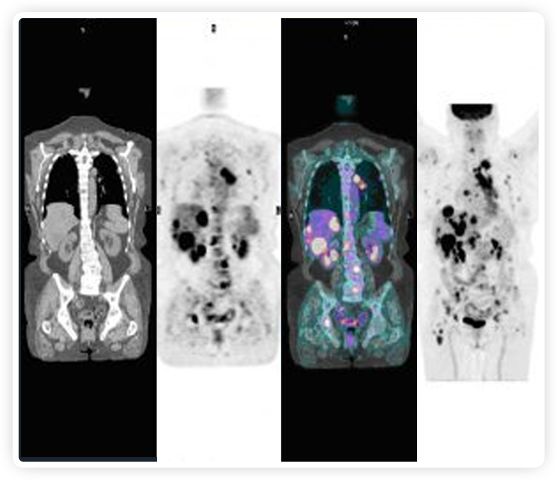

提起放療設備的引導系統(tǒng),大家通常會想到結構性成像的CT或核磁。但你有沒有想過用功能性成像來引導放療呢?美國的一家醫(yī)療器械公司從2011年就致力于研究開發(fā)用PET提供生物學指導放射治療的設備BgRT。BgRT能實時利用癌癥的生物學特征作為信號指導治療全身腫瘤。

到目前為止,放射腫瘤學中(使用的圖像主要是結構性的,而PET圖像可以提供生物學信息。通過使用注射示蹤劑,例如18-FDG,PET可以描繪腫瘤的代謝活性,使其“點亮”。(FDG是用于可視化癌癥代謝的最廣泛使用的示蹤劑。與正常組織相比,腫瘤細胞保留更高水平的FDG。)不同的PET示蹤劑可以識別腫瘤的不同生物學特征,例如特定生物標志物抗原(例如,PSMA)或甚至探測免疫系統(tǒng)本身(例如,PDL1表達或活化的T細胞)。

PET+放療共同治療

RefleXion將PET成像與立體定向放射治療相結合。在注射示蹤劑后,RefleXion的技術基于示蹤劑信號實時地在一個或多個目標上引導治療性X射線。使用這種專有方法,RefleXion的平臺有可能比現(xiàn)有系統(tǒng)向癌癥病變提供更高劑量的輻射,并改善周圍健康組織的保護。